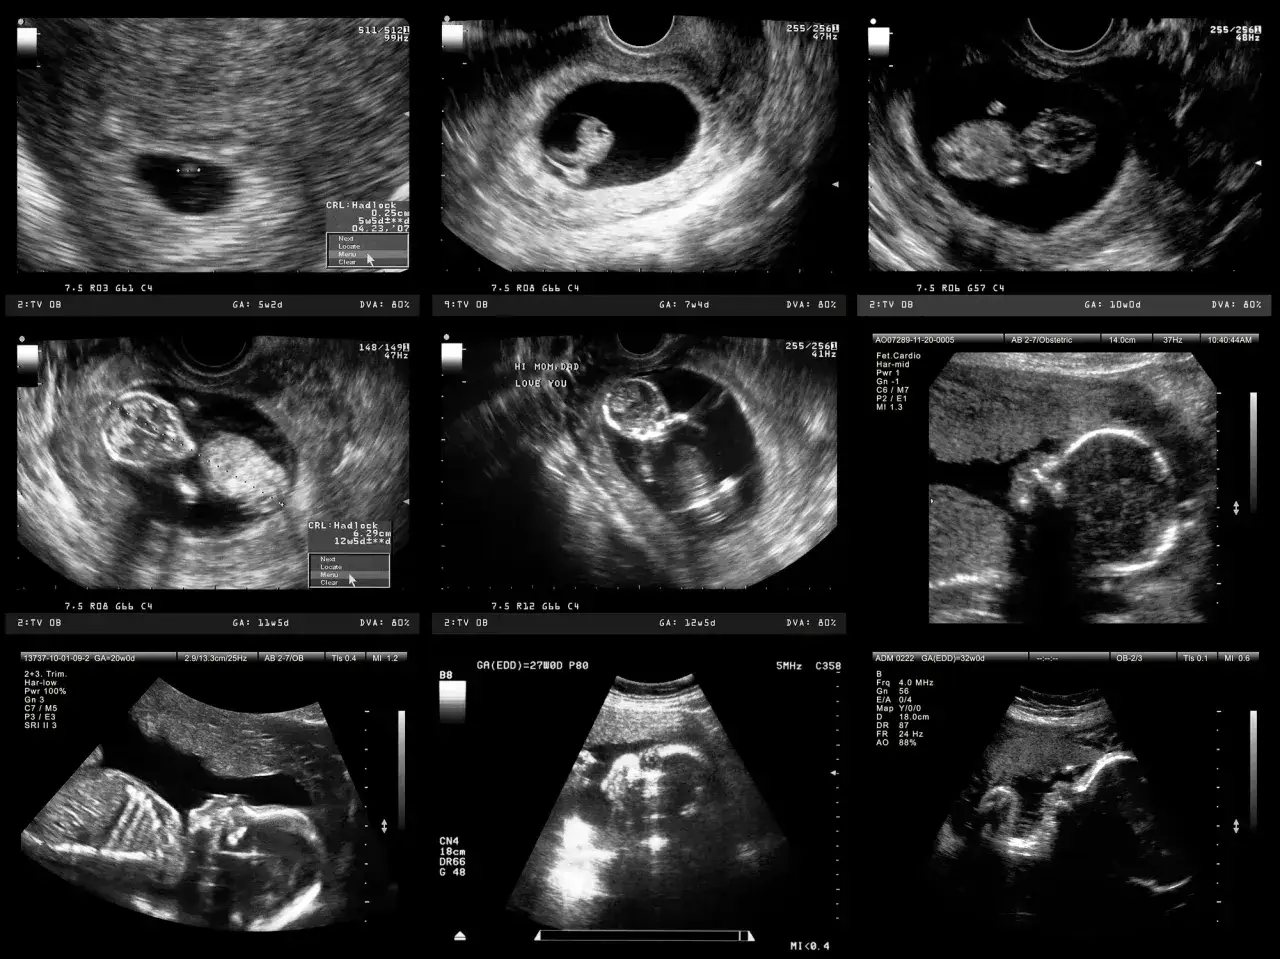

Jednym z najważniejszych badań przesiewowych w pierwszym trymestrze jest USG genetyczne, często nazywane też USG I trymestru lub USG przezierności karkowej (NT). Wykonuje się je w bardzo precyzyjnym oknie czasowym: między 11. a 14. tygodniem ciąży, a dokładniej między 11 tygodniem i 0 dni a 13 tygodniem i 6 dni. W tym okresie płód ma odpowiednią wielkość, aby lekarz mógł dokładnie ocenić kluczowe markery.

Podczas tego badania lekarz ocenia m.in. przezierność karkową (NT), kość nosową, przepływ krwi w przewodzie żylnym i zastawce trójdzielnej serca. Równolegle, lub w niewielkim odstępie czasu, wykonuje się test PAPP-A (test podwójny), czyli badanie krwi matki, które mierzy stężenie dwóch białek: PAPP-A i wolnej podjednostki beta-hCG. Połączenie wyników USG i testu PAPP-A pozwala na wyliczenie skorygowanego ryzyka wystąpienia najczęstszych wad genetycznych, takich jak zespół Downa (trisomia 21), zespół Edwardsa (trisomia 18) i zespół Patau (trisomia 13). To badanie jest kluczowe i stanowi podstawę dalszych decyzji diagnostycznych.

USG połówkowe, znane również jako USG morfologiczne, to jedno z najważniejszych badań w całej ciąży. Zazwyczaj wykonuje się je między 18. a 22. tygodniem ciąży. Jak sama nazwa wskazuje, jest to moment, w którym lekarz tworzy prawdziwą "mapę" rozwoju Twojego maluszka, szczegółowo analizując jego anatomię.

Podczas tego badania ginekolog dokładnie ocenia każdy narząd dziecka: serce (w tym jego budowę i przepływy), mózg, nerki, kręgosłup, kończyny, a także twarzoczaszkę. Sprawdza również ilość płynu owodniowego, lokalizację i budowę łożyska. Celem jest wykrycie ewentualnych wad wrodzonych narządów, które mogłyby wymagać dalszej diagnostyki lub interwencji po porodzie. To badanie daje nam mnóstwo cennych informacji o zdrowiu i rozwoju dziecka, a dla rodziców często jest to moment, w którym po raz pierwszy widzą swoje dziecko w tak szczegółowy sposób.

Ostatnie referencyjne badanie ultrasonograficzne, czyli trzecie USG, jest wykonywane zazwyczaj między 28. a 32. tygodniem ciąży. W tym czasie dziecko jest już duże, a jego narządy są w pełni ukształtowane, ale wciąż rośnie i dojrzewa.

Celem tego badania jest przede wszystkim ocena wzrastania płodu lekarz sprawdza, czy dziecko rozwija się w odpowiednim tempie, mierzy jego masę i porównuje z normami. Oceniane jest również ułożenie płodu (np. główkowe, pośladkowe), co ma znaczenie dla planowania porodu. Dodatkowo, lekarz kontroluje ilość płynu owodniowego, przepływy w naczyniach pępowinowych i macicznych, a także dojrzałość łożyska. To USG pozwala nam upewnić się, że dziecko ma optymalne warunki do dalszego rozwoju i jest dobrze przygotowane do narodzin, a także wykryć ewentualne późno ujawniające się wady.